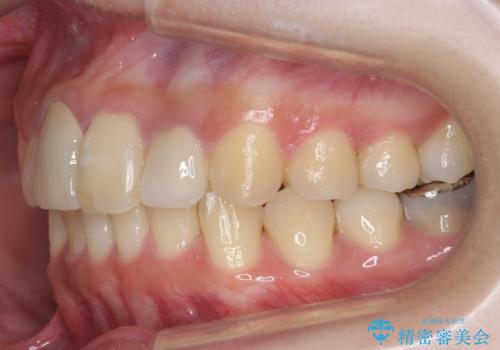

- 前歯のがたつきを主訴に来院。

保険治療の被せ物が前歯に2本あり、矯正治療で移動後にセラミックでやり替えを行っています。

右上のかみ合わせがずれていたため、インプラント矯正を行い、奥歯を後ろに下げて治療しています。